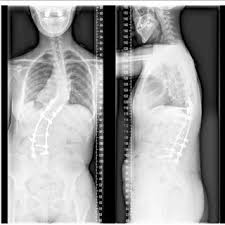

Shane Burgos Scoliosis : Mma Sun 2015 Prospect Spotlight The Featherweights 8 Shane Burgos Mma Sun : Burgos fez sua estreia no ufc em 9 de dezembro de 2016 no ufc fight night 102.. He's had scoliosis surgery and he's still out there fighting. Shane burgos was born on 19 march, 1991 in the bronx, new york, united states, is an american mma fighter. As a teenager, burgos underwent surgery for severe scoliosis and doctors told him he'd never be able to fight again. (joshu means assistant mixed martial arts instructor. Joshu shane burgos has studied for 9 years under sensei jose montes, the owner/instructor of tiger schulmann's mixed martial arts (tsmma) in vails gate, ny.

Learn how rich is he in this year and how he spends money? While complex in nature, medical breakthroughs are leading to exciting new treatment options that allow children with this condition to enjoy rich, full lives. Shane burgos is a top ufc fighter. Ufc fighter shane burgos overcame scoliosis at age 16. (joshu means assistant mixed martial arts instructor.

Patient Stories Scoliosis And Spine Associates from www.scoliosisassociates.com Carreira no mma ultimate fighting championship. Shane burgos was fighting his fourth straight fight from his own home state of new york. Viewed from the side, the normal spine takes the form of an elongated s, the upper back bowing outward and the lower back curving slightly inward. As of april 26, 2021, he is #9 in the ufc featherweight rankings. Shane burgos is a top ufc fighter. As a teenager, burgos underwent surgery for severe scoliosis and doctors told him he'd never be able to fight again. Ufc fighter shane burgos overcame scoliosis at age 16. Hey, i got mild scoliosis (spine curves) it doesn't affect me but in the future i want to turn pro in mma.

Three in every 1,000 people end up developing scoliosis at some point. Viewed from behind though, the spine should appear as a straight line from the base of the neck to the tailbone. As a teenager, burgos underwent surgery for severe scoliosis and doctors told him he'd never be able to fight again. The angle of the curve may be small, large, or somewhere in between. Edson barboza, with official sherdog mixed martial arts stats, photos, videos, and more for the featherweight fighter from.

Pdf Kyphoscoliosis With Klippel Trenaunay Syndrome A Case Report And Literature Review from www.researchgate.net The story in shanes's own words. As a teenager, burgos underwent surgery for severe scoliosis and doctors told him he'd never be able to fight again. Burgos discusses what he thought h. As a teenager, burgos underwent surgery for severe scoliosis and doctors told him he'd never be able to fight again. As of april 26, 2021, he is #9 in the ufc featherweight rankings. He's had scoliosis surgery and he's still out there fighting. Joshu shane burgos has studied for 9 years under sensei jose montes, the owner/instructor of tiger schulmann's mixed martial arts (tsmma) in vails gate, ny. As a teenager, burgos underwent surgery for severe scoliosis and doctors told him he'd never be able to fight again.

Mount sinai doctors manhasset 1155 northern boulevard manhasset, ny 11030. Joshu shane burgos has studied for 9 years under sensei jose montes, the owner/instructor of tiger schulmann's mixed martial arts (tsmma) in vails gate, ny. Scoliosis is a sideways curvature of the spine. Edson barboza, with official sherdog mixed martial arts stats, photos, videos, and more for the featherweight fighter from. Three in every 1,000 people end up developing scoliosis at some point. (joshu means assistant mixed martial arts instructor. But after refusing to give up on his goal, burgos is now earning plenty of admirers in the ufc. Also learn how he earned most of networth at the age of 29 years old? While complex in nature, medical breakthroughs are leading to exciting new treatment options that allow children with this condition to enjoy rich, full lives. I know nate quarry had a slipped disc and back surgery, tito ortiz had back surgery, and. He's had scoliosis surgery and he's still out there fighting. The squeaks have been silenced for about a year now, but not before shane burgos risked his health to pursue his dream. Original poster 1 point · 1 year ago.